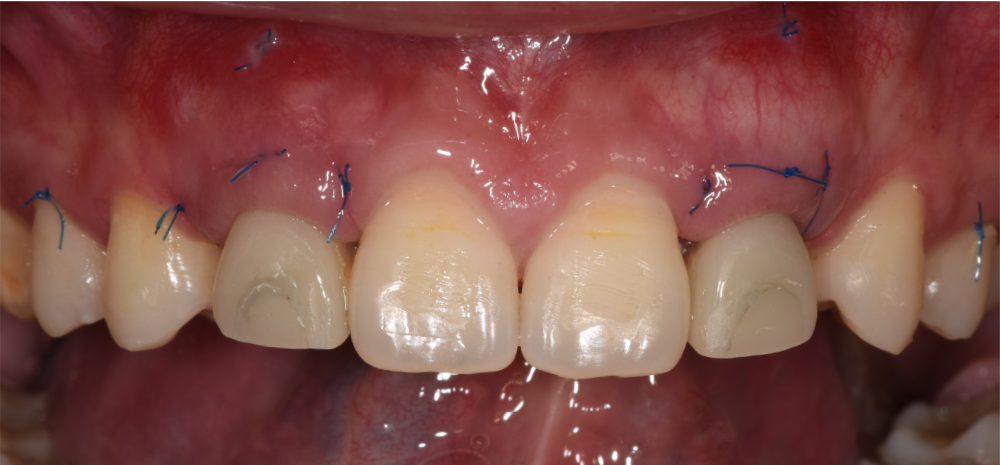

就位临时基台并将预成的树脂牙冠在口内Pick-Up

白色箭头示黑三角,原因分析:

1.因不是即刻种植,龈乳头处的软组织已是平坦的,缝合后龈乳头的形态欠佳

2.龈缘位置(黄色尖头示)较理想龈缘偏冠方,临时修复体颈部关键区凸起造成张力

改进:先将临时修复体关键区设计在冠根方,先确保龈乳头愈合良好,后期再塑形

戴入临时修复体正面观

术后10天拆线,龈乳头处软组织较术后有所改善

术后10天拆线,唇侧褥式缝合保留未拆,拆线后取模制作保持器